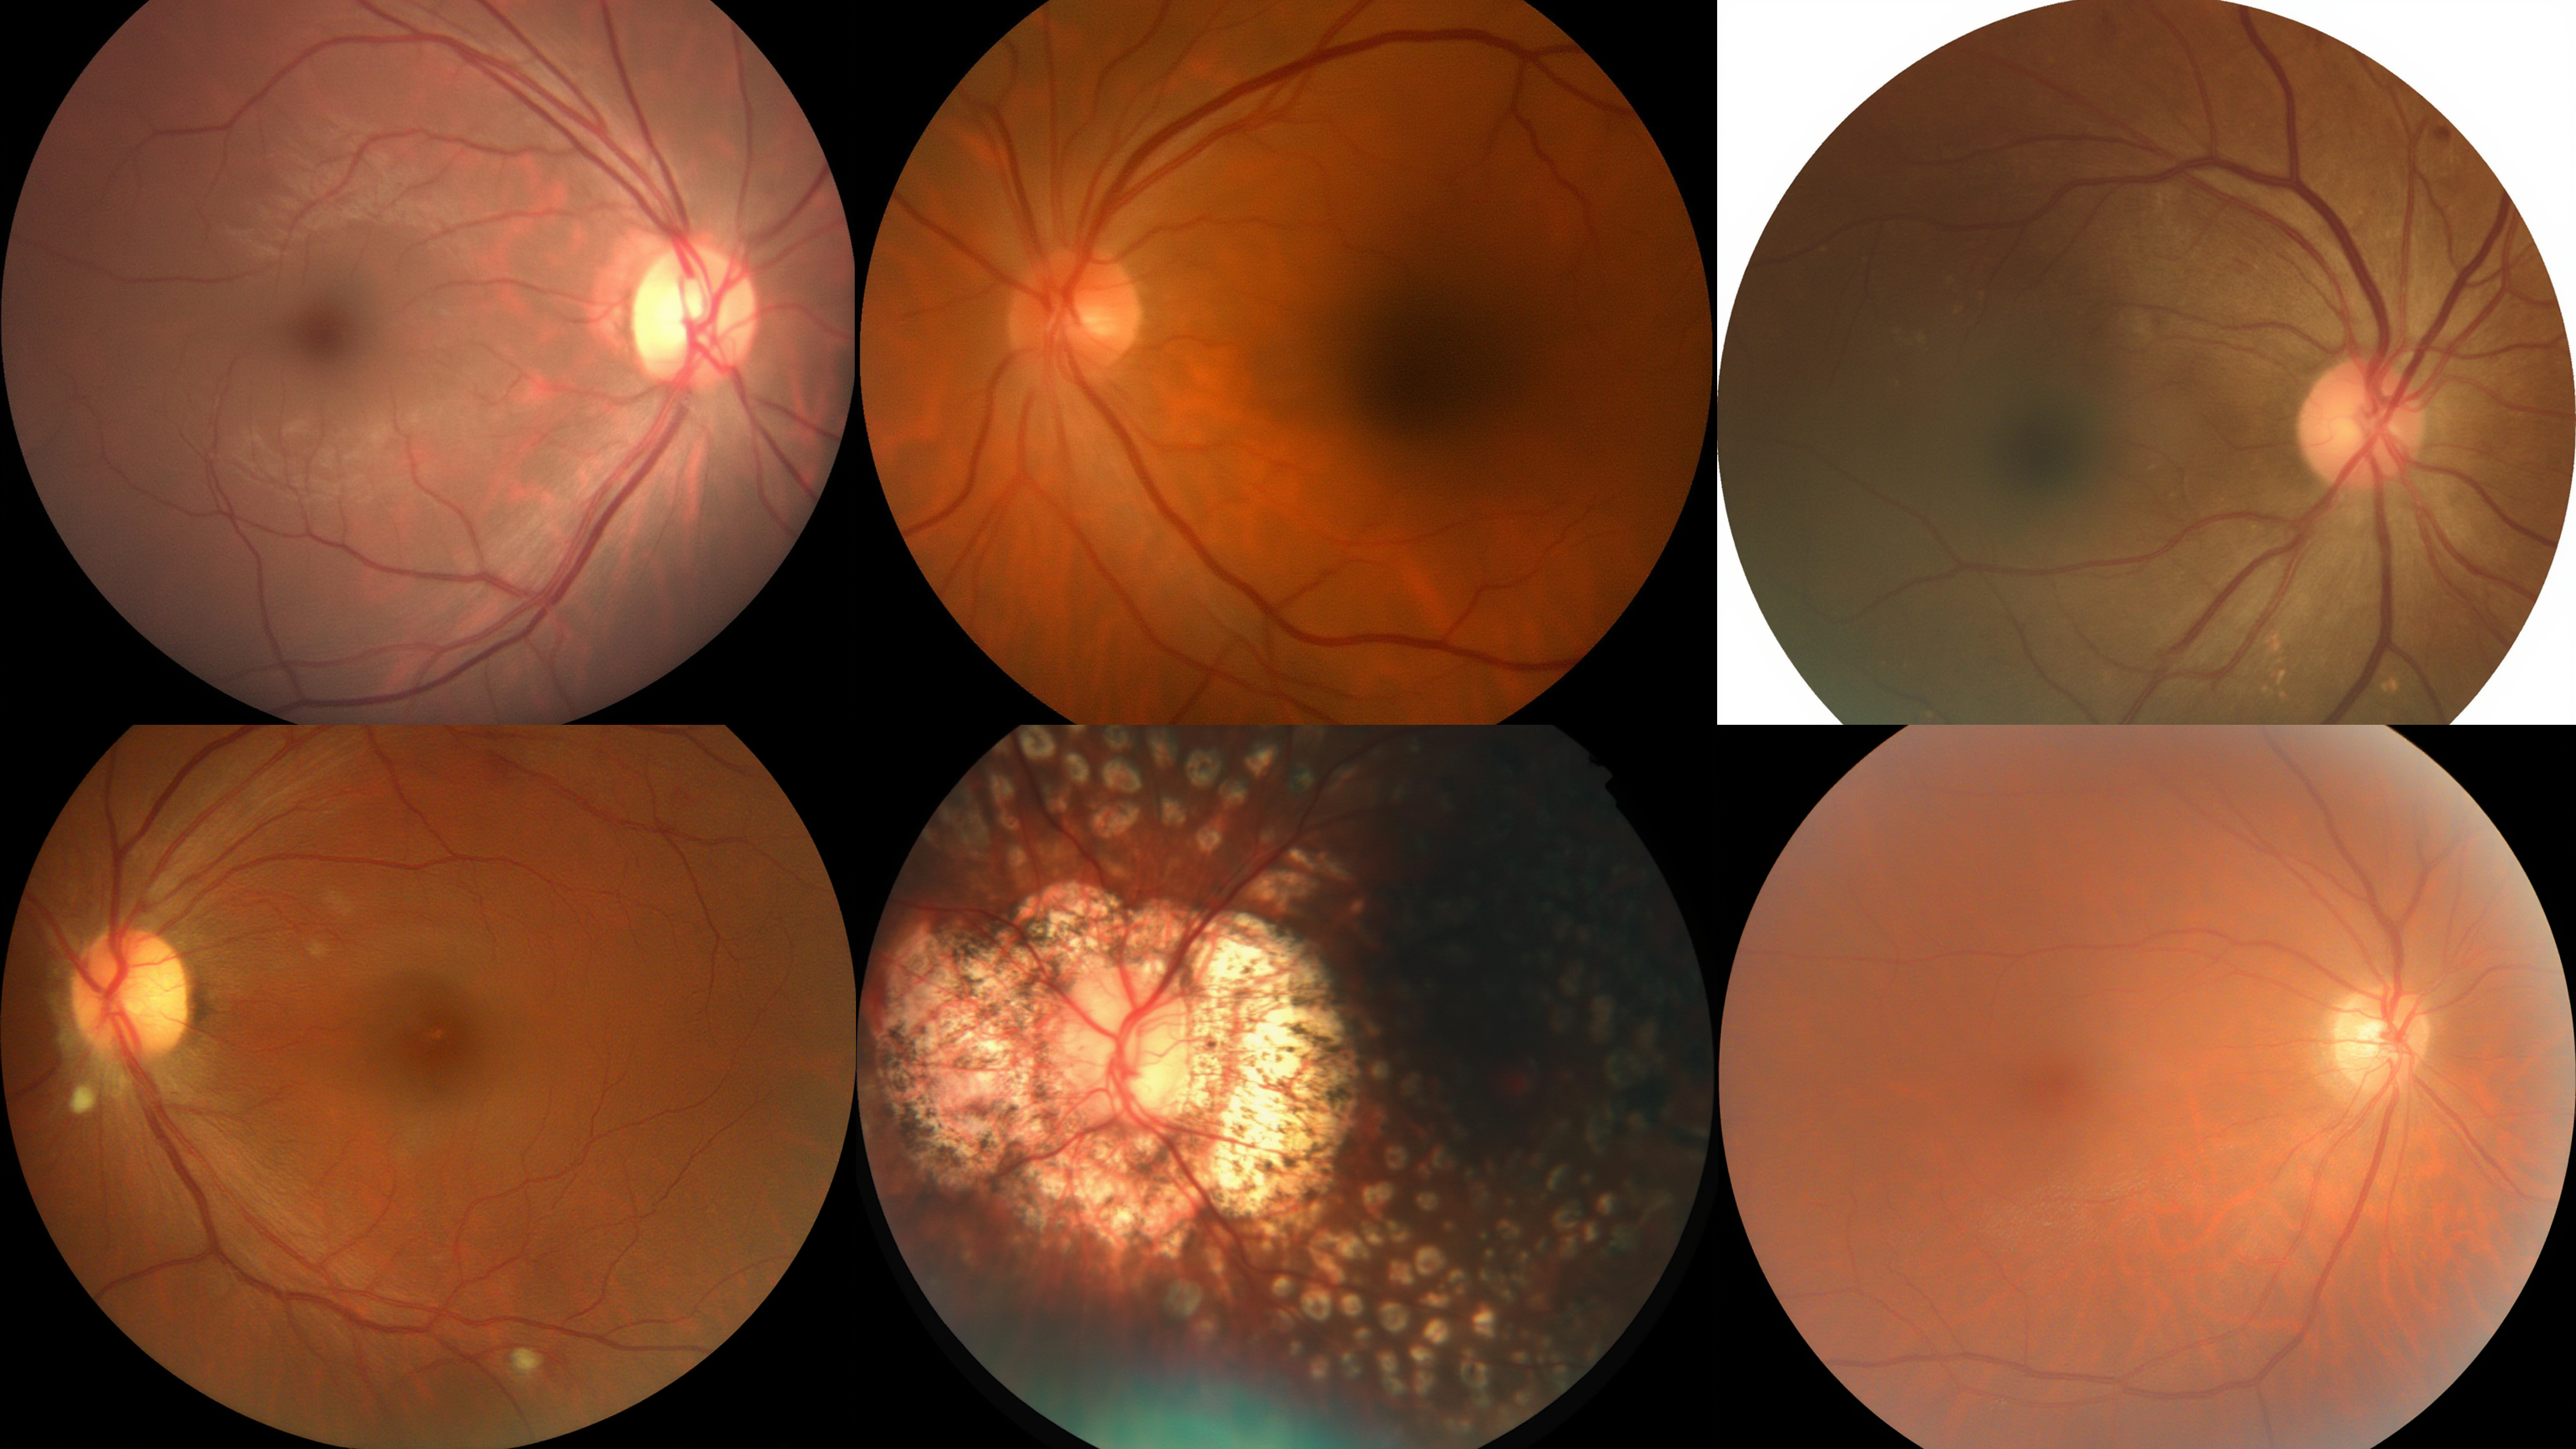

Text-to-medical-image generation results showing high-quality synthesis

Additional text-to-medical-image generation examples across modalities

Medical-Image Generation across 8 modalities

Retinal Fundus Photography (CFP)

Optical Coherence Tomography (OCT)

Endoscopy